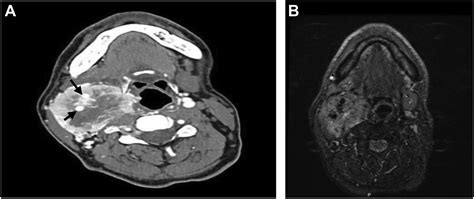

Diagnosing a Carotid Body Tumor requires a combination of physical examination and advanced imaging studies. When a physician suspects such a growth, they typically use specific diagnostic tools to differentiate it from enlarged lymph nodes or other neck masses. The “Lyre sign,” seen on imaging, is a classic finding where the internal and external carotid arteries are splayed apart by the tumor mass.

CT Angiography (CTA) Provides detailed views of the tumor's size and its relationship to major arteries.

Magnetic Resonance Imaging (MRI) Offers excellent soft-tissue contrast to identify involvement of nerves.